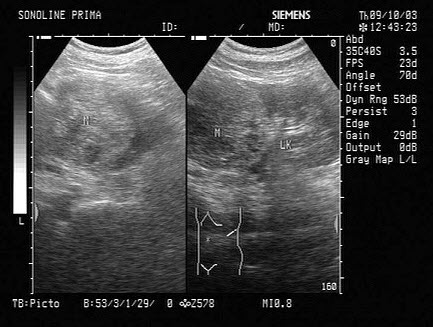

9、单项选择题

女,51岁,纳差、消瘦。结合超声声像图,诊断为()

A.胰腺癌

10、单项选择题

女,40岁,有时右上腹隐痛2年余。结合超声声像图,最可能的诊断为()